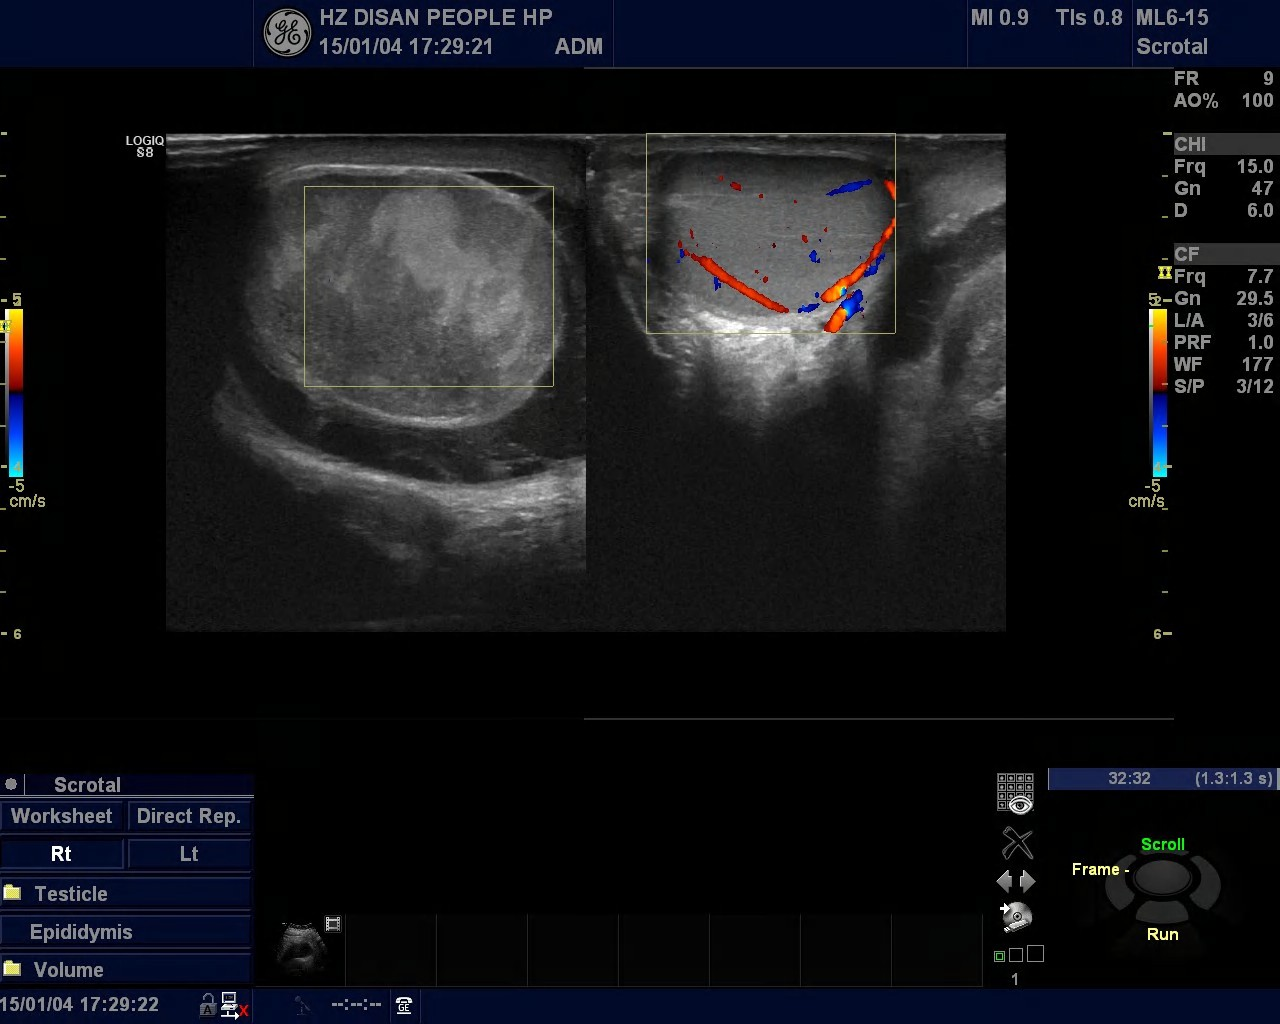

我院超聲科近期發(fā)現(xiàn)多例睪丸扭轉(zhuǎn)的病人。有一天下午超聲科來了一位下腹疼痛的男病人,醫(yī)生開了一張睪丸、附睪的彩超檢查單,后來檢查發(fā)現(xiàn)病人左側(cè)睪丸稍大、血流信號較右側(cè)減少,未排除睪丸扭轉(zhuǎn)可能,建議進(jìn)一步檢查。泌尿外科醫(yī)生看到檢查報告單,加上病人的臨床癥狀,考慮左側(cè)睪丸扭轉(zhuǎn)。醫(yī)生建議急診手術(shù),手術(shù)結(jié)果證明是睪丸扭轉(zhuǎn)。如果病人再晚一點(diǎn)就診或手術(shù)的話,病人的睪丸就會壞死,恐怕只能悲催地手術(shù)切除了。

睪丸扭轉(zhuǎn)(torsion of testis)又稱精索扭轉(zhuǎn),與陰囊先天性解剖發(fā)育異常密切相關(guān),包括精索過長,精索鞘膜附著異常形成“鐘擺式”睪丸以及睪丸引帶缺如等。深睡眠、劇烈運(yùn)動、撞擊等狀態(tài),可使精索上的提睪肌強(qiáng)烈收縮,導(dǎo)致扭轉(zhuǎn)并引起睪丸的急性血液循環(huán)障礙,臨床并不罕見。

睪丸扭轉(zhuǎn)為泌尿外科常見急癥之一。睪丸扭轉(zhuǎn)會使睪丸的血液供應(yīng)減少,如果不及時發(fā)現(xiàn)并解除 ,就可導(dǎo)致睪丸壞死。一般來說 ,扭轉(zhuǎn)后 6小時內(nèi) ,可采用手術(shù)緩解扭轉(zhuǎn) ,既可保留睪丸不影響生育 ,又可預(yù)防復(fù)發(fā)。扭轉(zhuǎn)超過6小時,睪丸不容易救活,一旦壞死 ,不得不“忍痛割愛”,予以手術(shù)切除。

睪丸既是生殖器官,又是內(nèi)分泌器官,對于男性的重要性不言而喻。所以,我院泌尿科醫(yī)生建議,如果出現(xiàn)睪丸疼痛,沒有好轉(zhuǎn)反而越來越疼的話,要特別警惕有無睪丸扭轉(zhuǎn),趕緊去醫(yī)院就診。睪丸扭轉(zhuǎn)一旦確診,應(yīng)及時進(jìn)行手術(shù),即使懷疑有扭轉(zhuǎn),也應(yīng)盡早手術(shù)探查。如果病人沒有及時就醫(yī)可能會造成無法挽回的嚴(yán)重后果。(超聲科 馬李明)